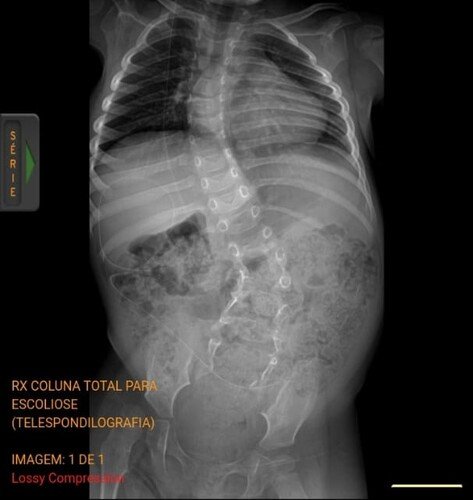

Sou mãe de uma menina, Lorena, de 2 anos e 8 meses, portadora das sequelas da mielomeningocele e chiari II, que está agora com o diagnóstico de escoliose, duas vértebras formaram-se juntas fazendo um formato de triângulo em meio a coluna, prendendo a medula e fazendo com que ela se curve rapidamente, por estar em fase de crescimento é uma cirurgia de emergência, pois quanto mais tempo passa mais a coluna se curva por conta do crescimento. Esta cirurgia tem uma espera muito longa via SUS e via judicial, por este motivo estamos tentando juntar o dinheiro do orçamento medico para fazermos o quanto antes.